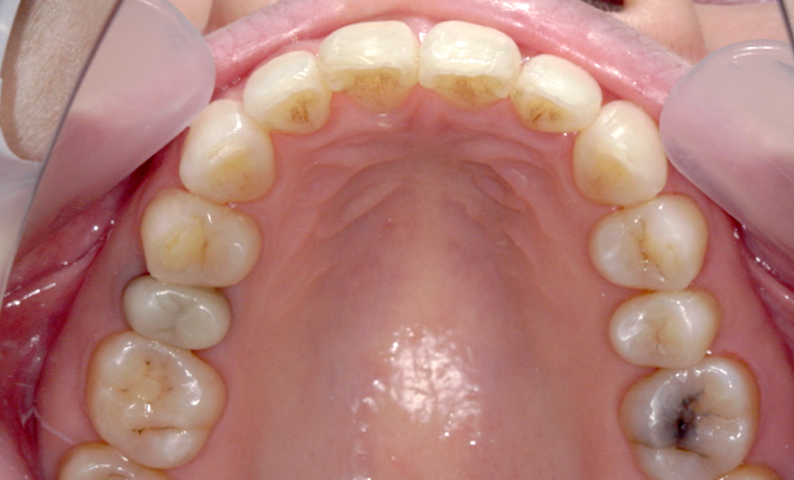

症例_002 下顎だけの部分矯正

治療期間:6ヶ月金額:21万円+税女性前歯のデコボコ下の前歯だけ

| Before | After |